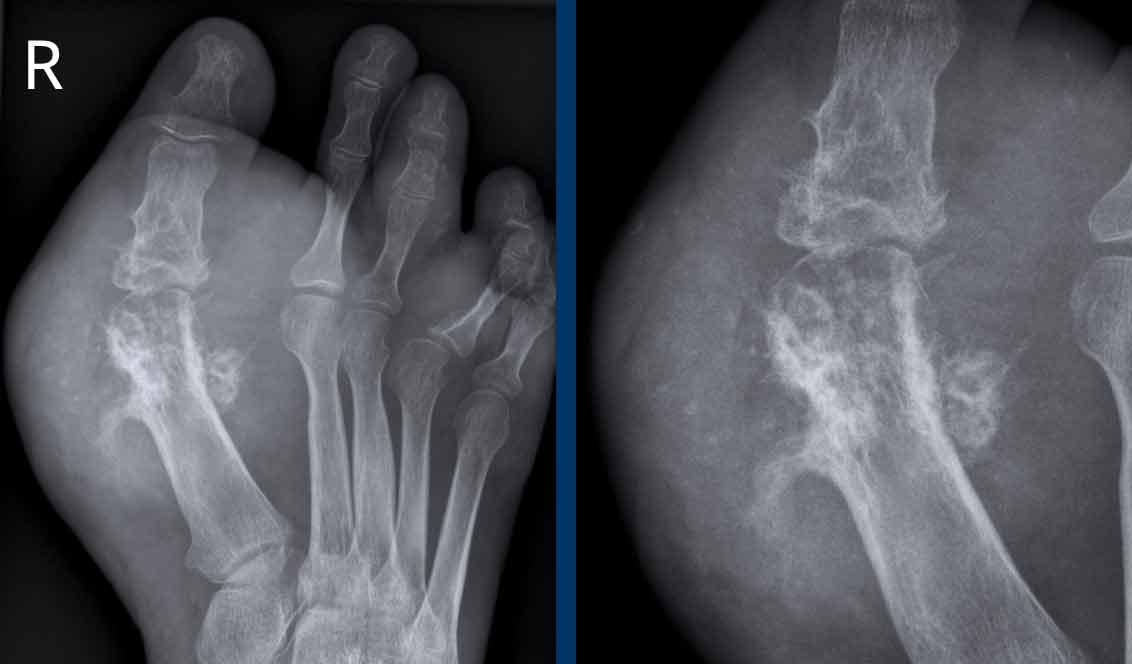

Ngón xúc xích

Hình ảnh điển hình của viêm ngón tay (dactylitis) “ngón xúc xích” với phù nề mô mềm và biến dạng bút chì trong cốc tại khớp liên đốt xa (DIP) 1-2 và 5 của bàn tay trái ở bệnh nhân viêm khớp vảy nến.

Lưu ý rằng các khớp bàn ngón tay (MCP) không bị tổn thương (khác với viêm khớp dạng thấp).

Viêm khớp vảy nến tiến triển

- Hình bên trái cho thấy bào mòn xương ở rìa khớp (mũi tên đen) và hình thành xương mờ nhạt (mũi tên xanh) tại khớp liên đốt ngón (IP).

- Về sau, bệnh tiến triển thành biến dạng bút chì trong cốc điển hình.

Phân bố tổn thương và sự hình thành xương khiến chẩn đoán viêm khớp dạng thấp ít có khả năng.

Các bào mòn xương ở rìa khớp và sự vắng mặt của tổn thương khớp liên đốt xa (DIP) ở các khớp khác khiến chẩn đoán viêm xương khớp bào mòn ít có khả năng, mặc dù biến dạng bút chì trong cốc có thể trông giống biến dạng cánh hải âu trong viêm xương khớp bào mòn.